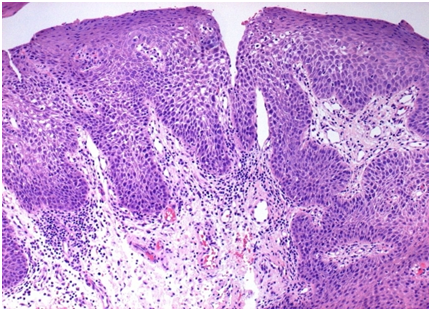

Also ratified as benign migratory glossitis, is characterized by multiple zones of distinct red and white (geographic tongue). Typically prevalent in the females and children, the oral inflammatory condition of obscure aetiology. Atopy and psoriaisis coexist. Atrophy of the filiform papillae, central erythema with yellow to white raised perimeter arise in the lesions of the tongue. Exacerbations and a migrating pattern is demonstrable in what is a chiefly asymptomatic lesion. Taste is not affected. The precise, diagnostic manifestation needs to be distinguished from oral candida infection (Figure 1).

A diffuse chronic inflammatory mucocutaneous disease categorized by cutaneous lesions which are multiple, pruritic, purplish, polygonal papules. Extensor surface dermatological lesions manifest minimal inflammation of indeterminate aetiology occurring in 1 to 2% of the adults. Immune mediation by CD8+ cytotoxic T cells incites epithelial apoptosis. The condition occurs at all ages, peaking at 40 years of age. Female to male ratio is 1.4: 1.Two dominant clinical forms prevail: reticular and erosive. The reticular configuration is bilateral and asymptomatic with white lacy striations (Wickham’s Striate) or papules on the posterior buccal mucosa, similar to leukoplakia. The erosive form elucidates erythema, tenderness and painful ulcers with peripheral, white radiating striae. Desquamative gingivitis displays generalized erythema and gingival ulceration. Reticular lesions can be clinically classified and standardized. A diagnostic biopsy is required for ambiguous, non specific lesions. Oral lichen planus can be detected with oral cancer. Periodic follow-up of patients with tissue evaluation is essential for isolated lichen planus to exclude premalignant and malignant scenarios. Tobacco /Alcohol intake should be curbed. The condition needs to be differentiated from drug reactions, graft versus host disease, oral contact stomatitis due to dental materials (amalgam) Erosive form require demarcation from systemic lupus erythromatosus, chronic ulcerative colitis. Gingival lesions resemble pemphigus vulgaris and pemphigoid. Immunofluorescence on tissue examination is diagnostic.